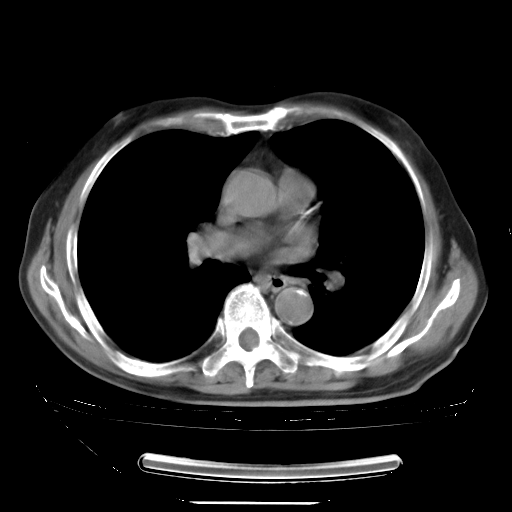

5月9日肺部CT(在4月27日齐鲁医院肺部CT描述部分肺组织磨玻璃样改变,12天后肺组织广泛磨玻璃样改变)

2009年5月9日肺部CT

大致读了系列胸部CT:纵隔窗无明显异常,肺窗:从4、27至今:主要是双肺中下野外带可见毛玻璃样改变,目前处于急性肺泡炎阶段,至于原因考虑1、结替组织或胶原血管性疾病所致?2、恶性疾病如恶组在肺部所致的表现或细支气管肺泡癌?3、药物或其它原因如肺蛋白沉着症所致肺泡炎目前不太可能?总之,明天就去请我院的呼吸科、感染科、血液科和临免专家会诊哈。